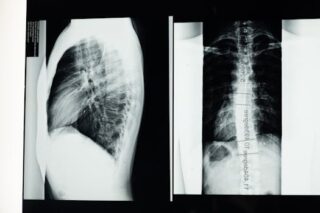

People with a desiccated spinal disc may experience symptoms like chronic back pain, stiffness, or a decreased range of motion. In some cases, there may be no noticeable symptoms until a related condition like a herniated disc develops. Diagnosing involves physical examination and imaging tests such as MRI or CT scans to assess the condition of the spinal discs.